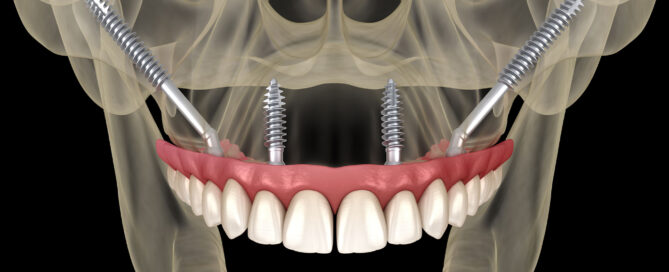

Enquanto o All-on-4 (ou All-on-Four) é indicado para pacientes com [...]

As doenças conhecidas por atrofia de maxila e atrofia de [...]